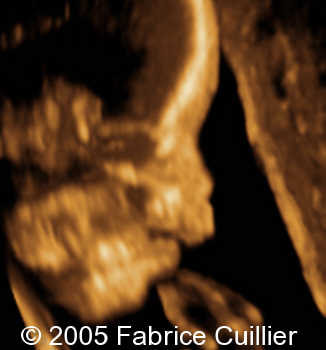

Cleft lip unilateral, 26 weeks

The following are the ultrasound images of a fetus with unilateral cleft lip, discovered at 26 weeks of gestation.

3D rendered images: